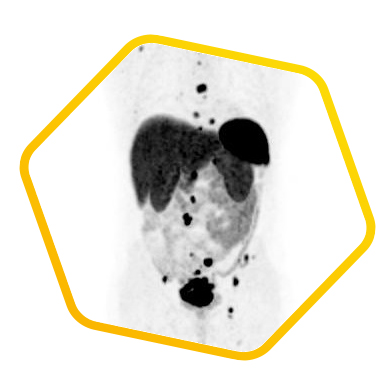

Dual tracer PET/CT (F-18 FDG and Ga-68 DOTATATE) are used for the metastatic evaluation of neuroendocrine tumor.

![]() [F-18] FDG |

![]() [Ga-68] DOTATATE |